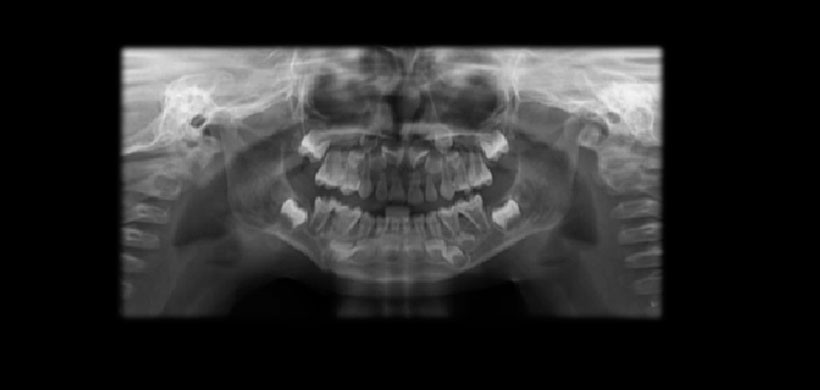

Figura 3: Radiografía panorámica mostrando las alteraciones en las dimensiones de la cámara pulpar de las molares deciduas mandibulares en ambos lados asociados a lesiones de caries.